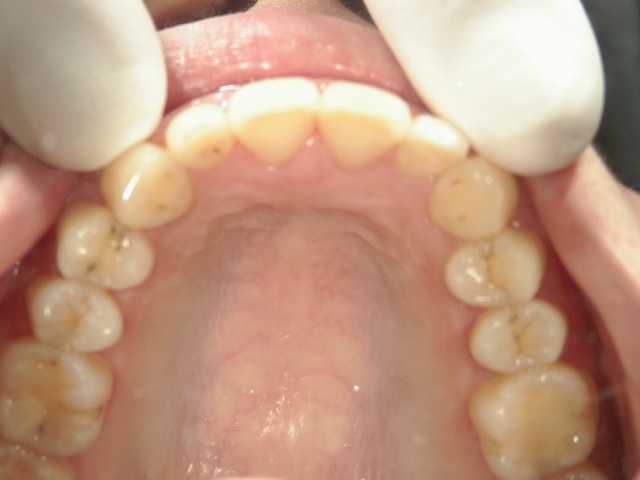

矯正歯科 治療前

矯正歯科 治療前 上顎